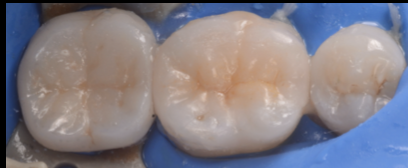

審美治療 30代セラミックオーバーレイセラミック治療マイクロスコープメタルフリー治療ラバーダムラバーダム女性歯がしみる歯が折れた歯が痛い神経を残したい被せ物が外れた見た目を綺麗に治したい詰め物に違和感銀歯が外れた銀歯をなくしたい 2025.06.18 【30代 女性】他院で入れたセラミックが虫歯になっている 治療前 治療後 治療後 担当医 生野 誠 主訴 他院で入れたセラミックが虫歯になっている 噛むと染みる 期間 2回 費用 10万 治療内容 セラミック治療 治療に伴うリスク セラミックの破折 関連症例